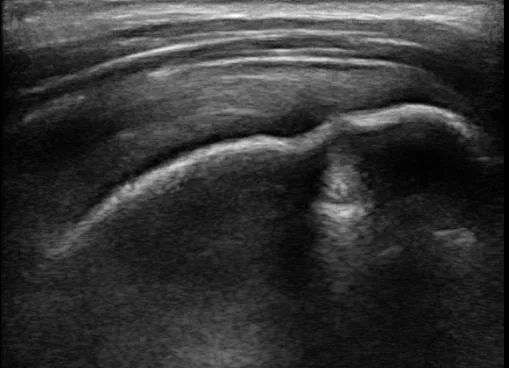

Musculoskeletal and procedure guidance ultrasound is a real-time, high-resolution imaging modality used to evaluate soft tissues, joints, tendons, ligaments, nerves, and bony surfaces, as well as to guide interventional procedures such as joint aspirations, injections, and biopsies. Its advantages include dynamic assessment, contralateral comparison, absence of ionizing radiation, portability, and the ability to visualize needle placement during interventions, which enhances procedural accuracy and safety.

The American Medical Society for Sports Medicine emphasizes that ultrasound guidance improves the precision and efficacy of musculoskeletal interventions, including aspirations, therapeutic injections, tenotomies, and hydrodissections, and is increasingly used for both established and advanced procedures in sports medicine